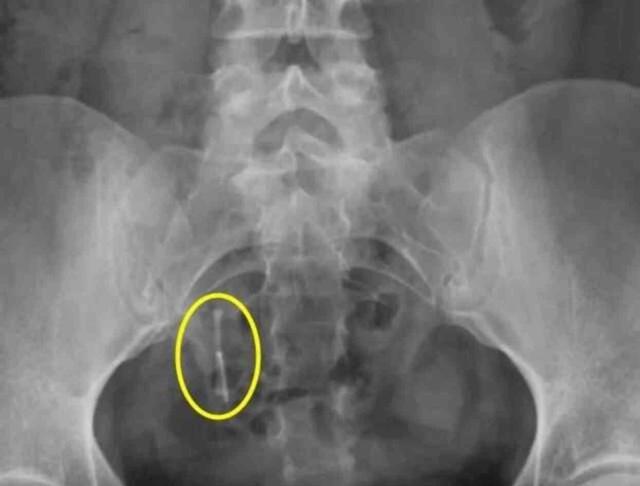

29 yaşındaki Daniella Hampton, 12 yıl önce kullandığı doğum kontrol cihazının rektumunda bulunmasından sonra büyük bir şok yaşadı. 2009 yılında rahmine yerleştirilen bakır spiral adı verilen intrauterin bir cihazı kullanmıştı. Altı hafta sonra düştüğü söylenmişti ve doktorlar cihazın varlığını teyit edememişti. Daniella, cihazın hâlâ vücudunda olduğuna inandı ve yıllarca ağrı çekti. Bir araba kazasında çekilen röntgen sonucunda cihazın rahmini delerek kalın bağırsağına yerleştiği anlaşıldı.

İki çocuk annesi Daniella, yıllarca kısırlık tedavisi görmesine rağmen, aslında içinde bir doğum kontrol cihazı olduğunu bilmiyordu. Bir araba kazasında sonra çekilen röntgen sonucunda cihazın rahmini delerek kalın bağırsağına yerleştiği anlaşıldı.